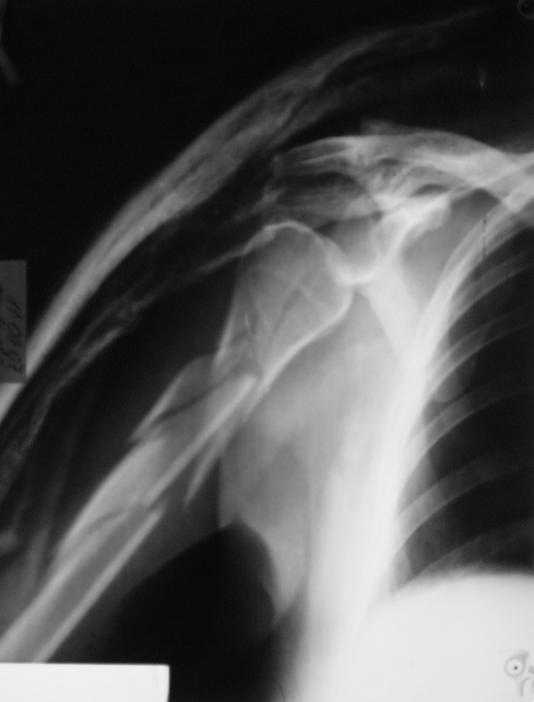

Re: Многооскольчатый перелом плечевой кости в В/3

Немножко переделал повязку с отведением, подправил, вот что получилось.

Перелом внутрисуставной, Вы уверены на счет Сармиенто? На первичном снимке не видно было перелома головки.

В наших условиях выбрали бы закрытое штифтование проксимальным гвоздем для плеча T2 Stryker. Голоку предварительно бы фиксировали спицами вне траектории гвоздя, чтобы не разобщить отломки.

Чтобы помочь определиться с выбором, и уточнить особенности выбранного варианта, надо знать, какие варианты доступны на месте.